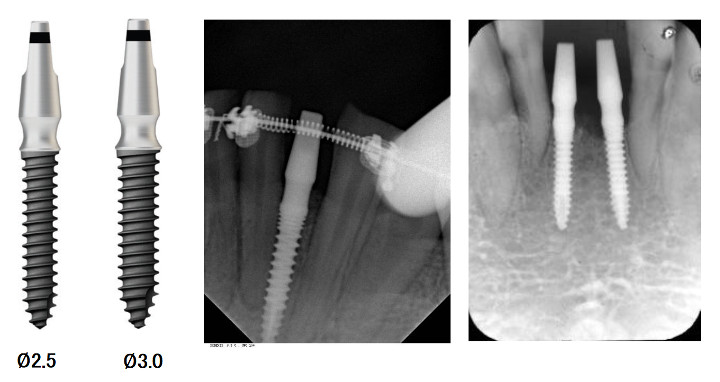

Имплантаты узкого диаметра Ø 2.5, Ø 3.0 специально разработаны для преодоления ограничений установки имплантатов стандартного диаметра в местах с недостаточной шириной кости.

- Монолитный (имплант и опорная головка (абатмент) составляют единое целое)

- Малый диаметр специально для узкого гребня